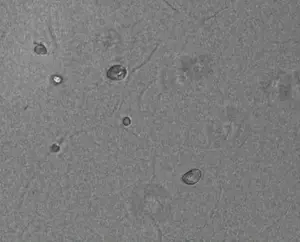

Dr. Ki Young Kim and her team at the Korea Research Institute of Chemical Technology (KRICT), in collaboration with Professor Laura Ha at Sunmoon University, have engineered a nanoparticle-stem cell hybrid, termed a nanobiohybrid by integrating mesoporous silica nanoparticles (mSiO₂ NPs) with human adipose-derived mesenchymal stem cells (hADMSCs). The resulting hybrid cells demonstrated markedly enhanced osteogenic (bone-forming) capability.